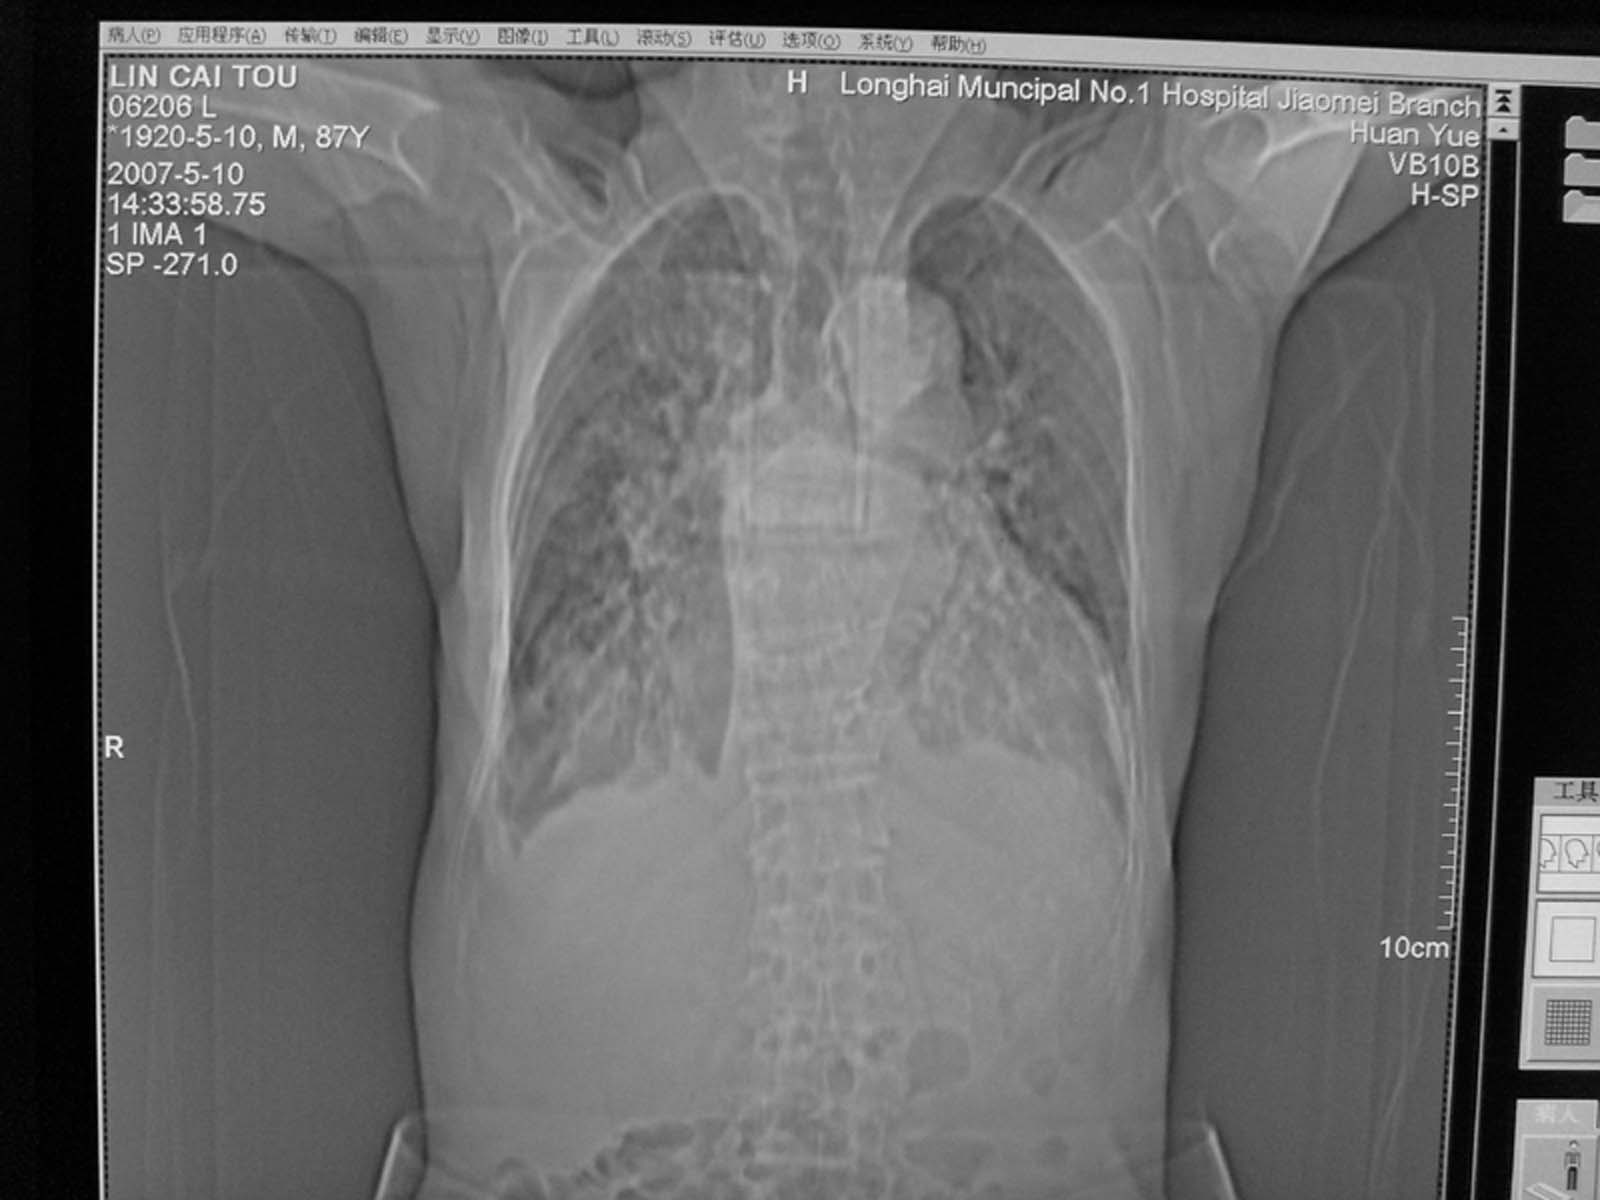

以下是引用小初学者在2007-5-12 16:26:00的发言:[br]1、心衰肺水肿两侧胸腔积液2、心包积液3、心瓣膜钙化